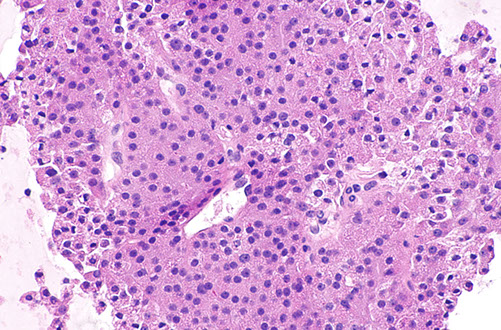

Parathyroid Carcinoma

Up to 2% of pts c hyperparathyroidism, M=F, ~50 yo, inc Ca2+, neck mass

- 1/3 have LN mets and 1/3 c distant mets at presentation

Micro: trabecular, thick fibrous bands, capsular invasion, mits, but need to see invasion into surrounding tissue or distant mets

IHC: (+) Cam5.2, AE1/AE3, PTH, CD56, SYN, CHR

- neg: TTF-1, thyroglobulin, PAX8, parafibromin

Genes: mutations in HRPT2/CDC73 gene on chr 1 which encodes parafibromin

- same gene is mutated in hyperparathyroidism-jaw tumor (HPT-JT) syndrome, which has ossifying fibromas of the jaw, uterine and renal tumors and parathyroid tumors

- PRAD 1, MEN 1, Cyclin D1 overexpression

Tx: surgery